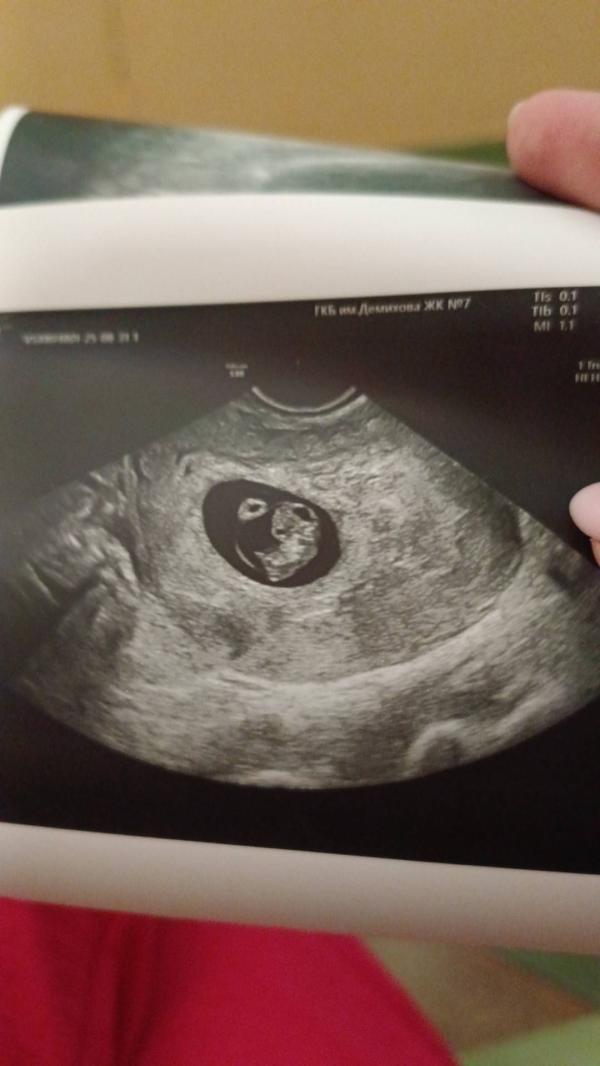

Сегодня мы ходили на УЗИ, поставили срок 7 недель 3 дня, сердечко бьётся, все хорошо. Лежит, балдеет в животике 🥰